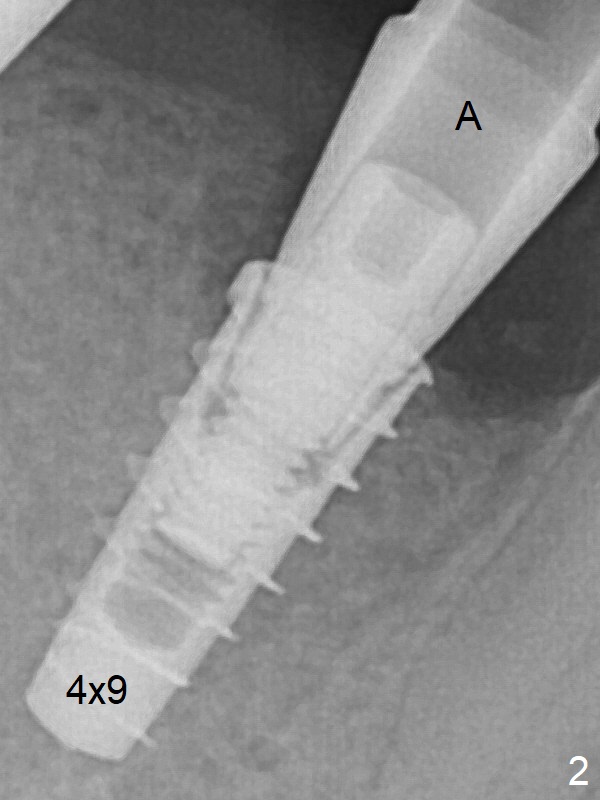

IBS种植体好像表面处理好,软硬组织愈合似乎很好,由于它使用五号钛合金,比四号钛合金硬(三倍),不容易断裂,所以毫米种植体用于狭窄的磨牙区仿佛没有问题,而绝大多数种植体使用四号钛合金。